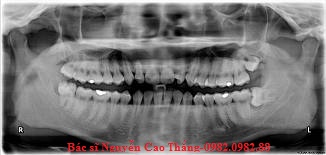

Phim XQ thể hiện bệnh nhân này có vấn đề về hướng mọc của răng trên cả 4 răng số 8 ở 4 góc hàm